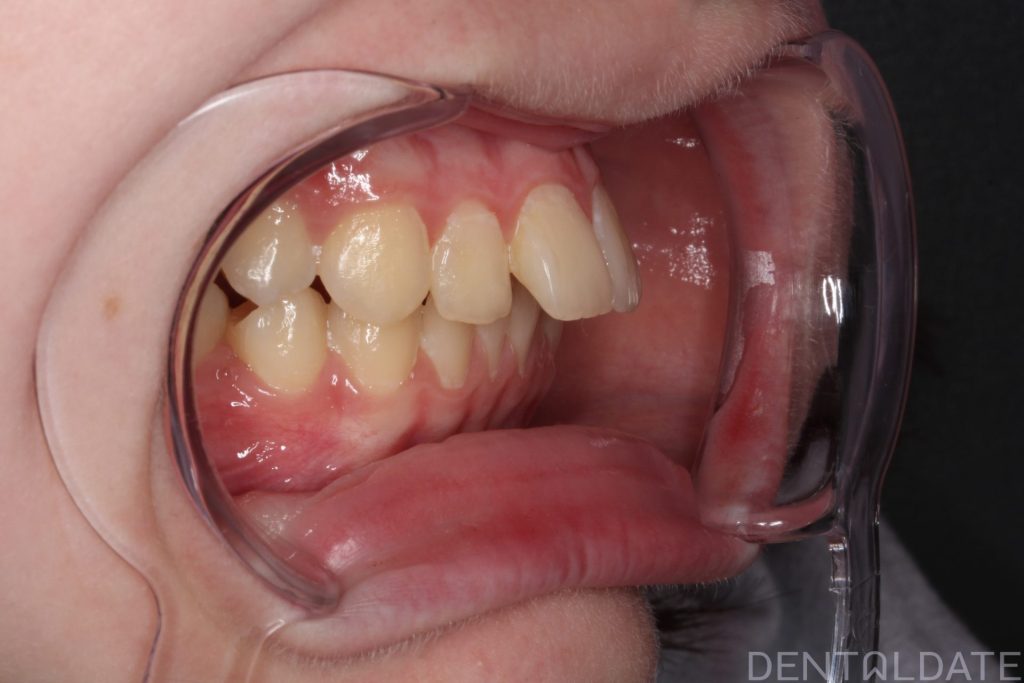

After a follow-up MRI confirmed the correct jaw position, braces were installed.

Orthodontic treatment lasted 10 months; currently, the patient is preparing for braces removal.